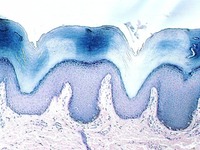

Stratified Columnar epithelium is rare. One place you can find it is in the largest ducts of salivary glands (parotid, submandibular, etc). The basal layer of cells are cuboidal cells and the layer nearest the apical surface includes columnar cells. The large droplets are mucus, in Goblet cells. This also illustrates the fact that epithelia are classified according to the cells nearest the lumen, in this case columnar.

Below is another view of a large (excretory) duct of a salivary gland showing the mucin in Goblet cells after a special stain. What might be the advantages of an epithelium that has a basal cuboidal cell layer and an apical columnar cell layer?